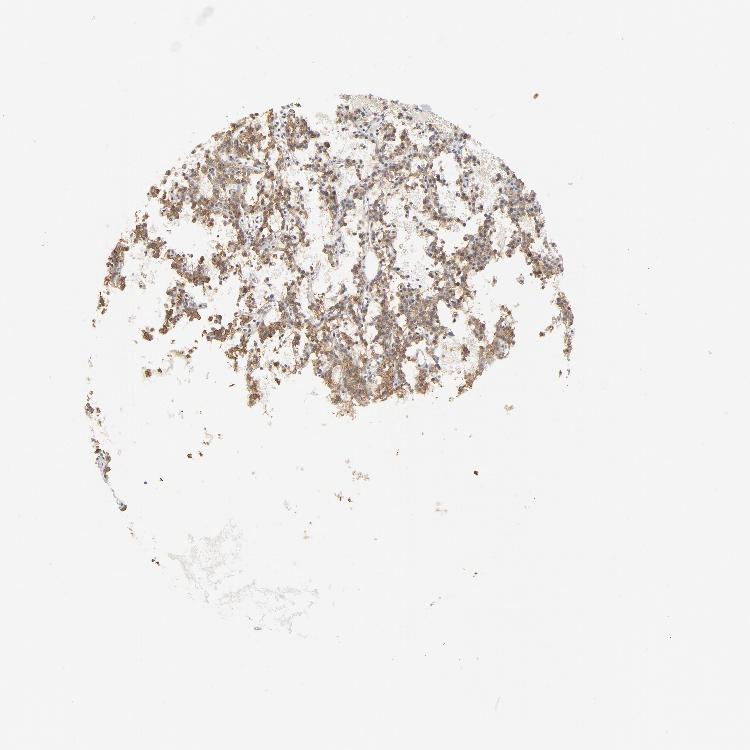

PARATHYROID GLAND - Antibody stainingi

Antibody staining in the annotated cell types in the current human tissue is reported as not detected, low, medium, or high, based on conventional immunohistochemistry profiling in selected tissues. This score is based on the combination of the staining intensity and fraction of stained cells.

Each image is clickable and will lead to virtual microscopy that enables deeper exploration of all samples and also displays staining intensity scores, fraction scores and subcellular localization as well as patient and tissue information for each sample.

Antibody HPA026761Antibody CAB003809Antibody CAB030012Antibody CAB055098

Glandular cells HighMediumHighHigh